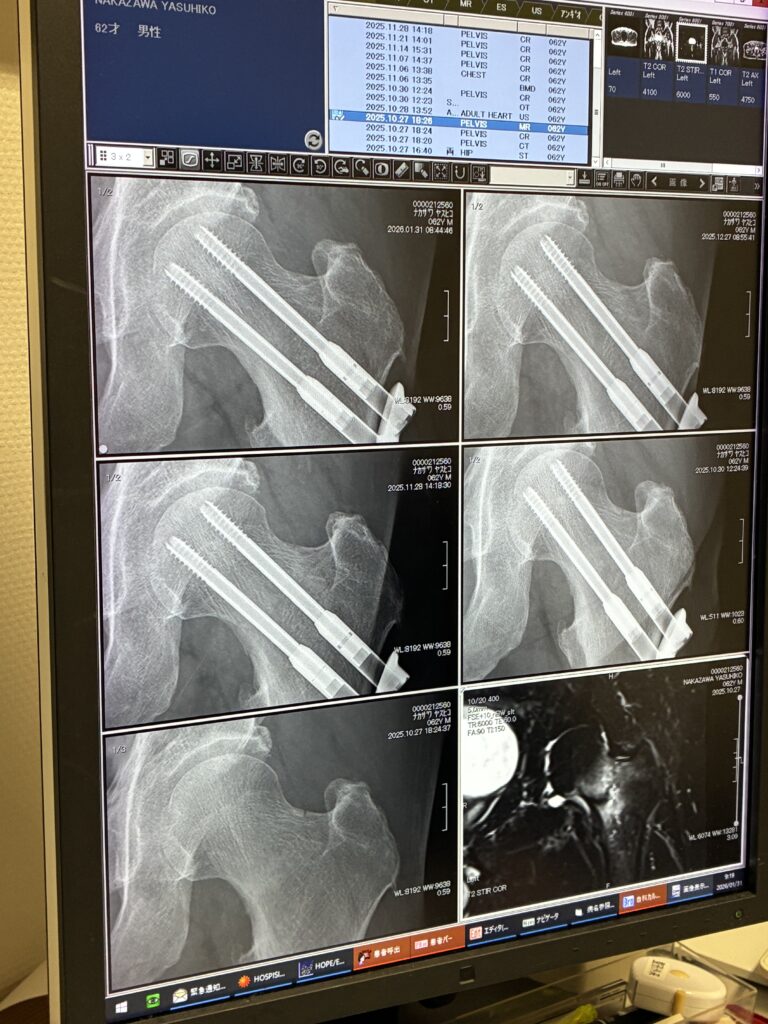

レントゲンを撮って骨折部のつながり具合を診てもらったわけですが、画像を見ても素人には全然わかりません(笑)。でも先生の話では、治癒の具合は優秀とのこと。これは整体院のオステオトロンの効果かもしれませんね。